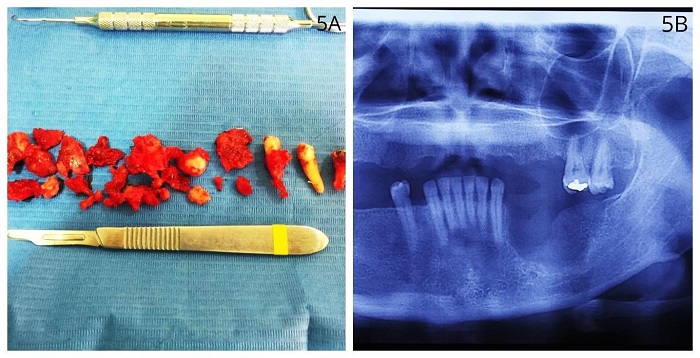

Se decidió eliminar la lesión, extraer los dientes comprometidos (segundo premolar y primer molar inferiores izquierdos) y efectuar remodelado. Para comprobar la exéresis total de la lesión (figura 5) se tomó una radiografía y se envió nuevamente a análisis de patología, cuyos cortes mostraron una lesión fibrósea benigna constituida por numerosas trabéculas óseas curvilíneas, con apariencia de “letras chinas”, sin recubrimiento osteoblástico e inmersas en un estroma de tejido fibroso moderadamente celular, sin atipias. El diagnóstico fue DF (figura 6).